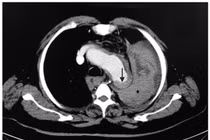

(khoahocdoisong.vn) - Bệnh viện quận Thủ Đức TPHCM vừa tiến hành can thiệp đặt stent-graft cho một bệnh nhân cao tuổi bị phình động mạch chủ bụng. Đây đã là ca thứ 4 thành công trong thời gian ngắn triển khai kỹ thuật cao cấp tại một bệnh viện tuyến quận.